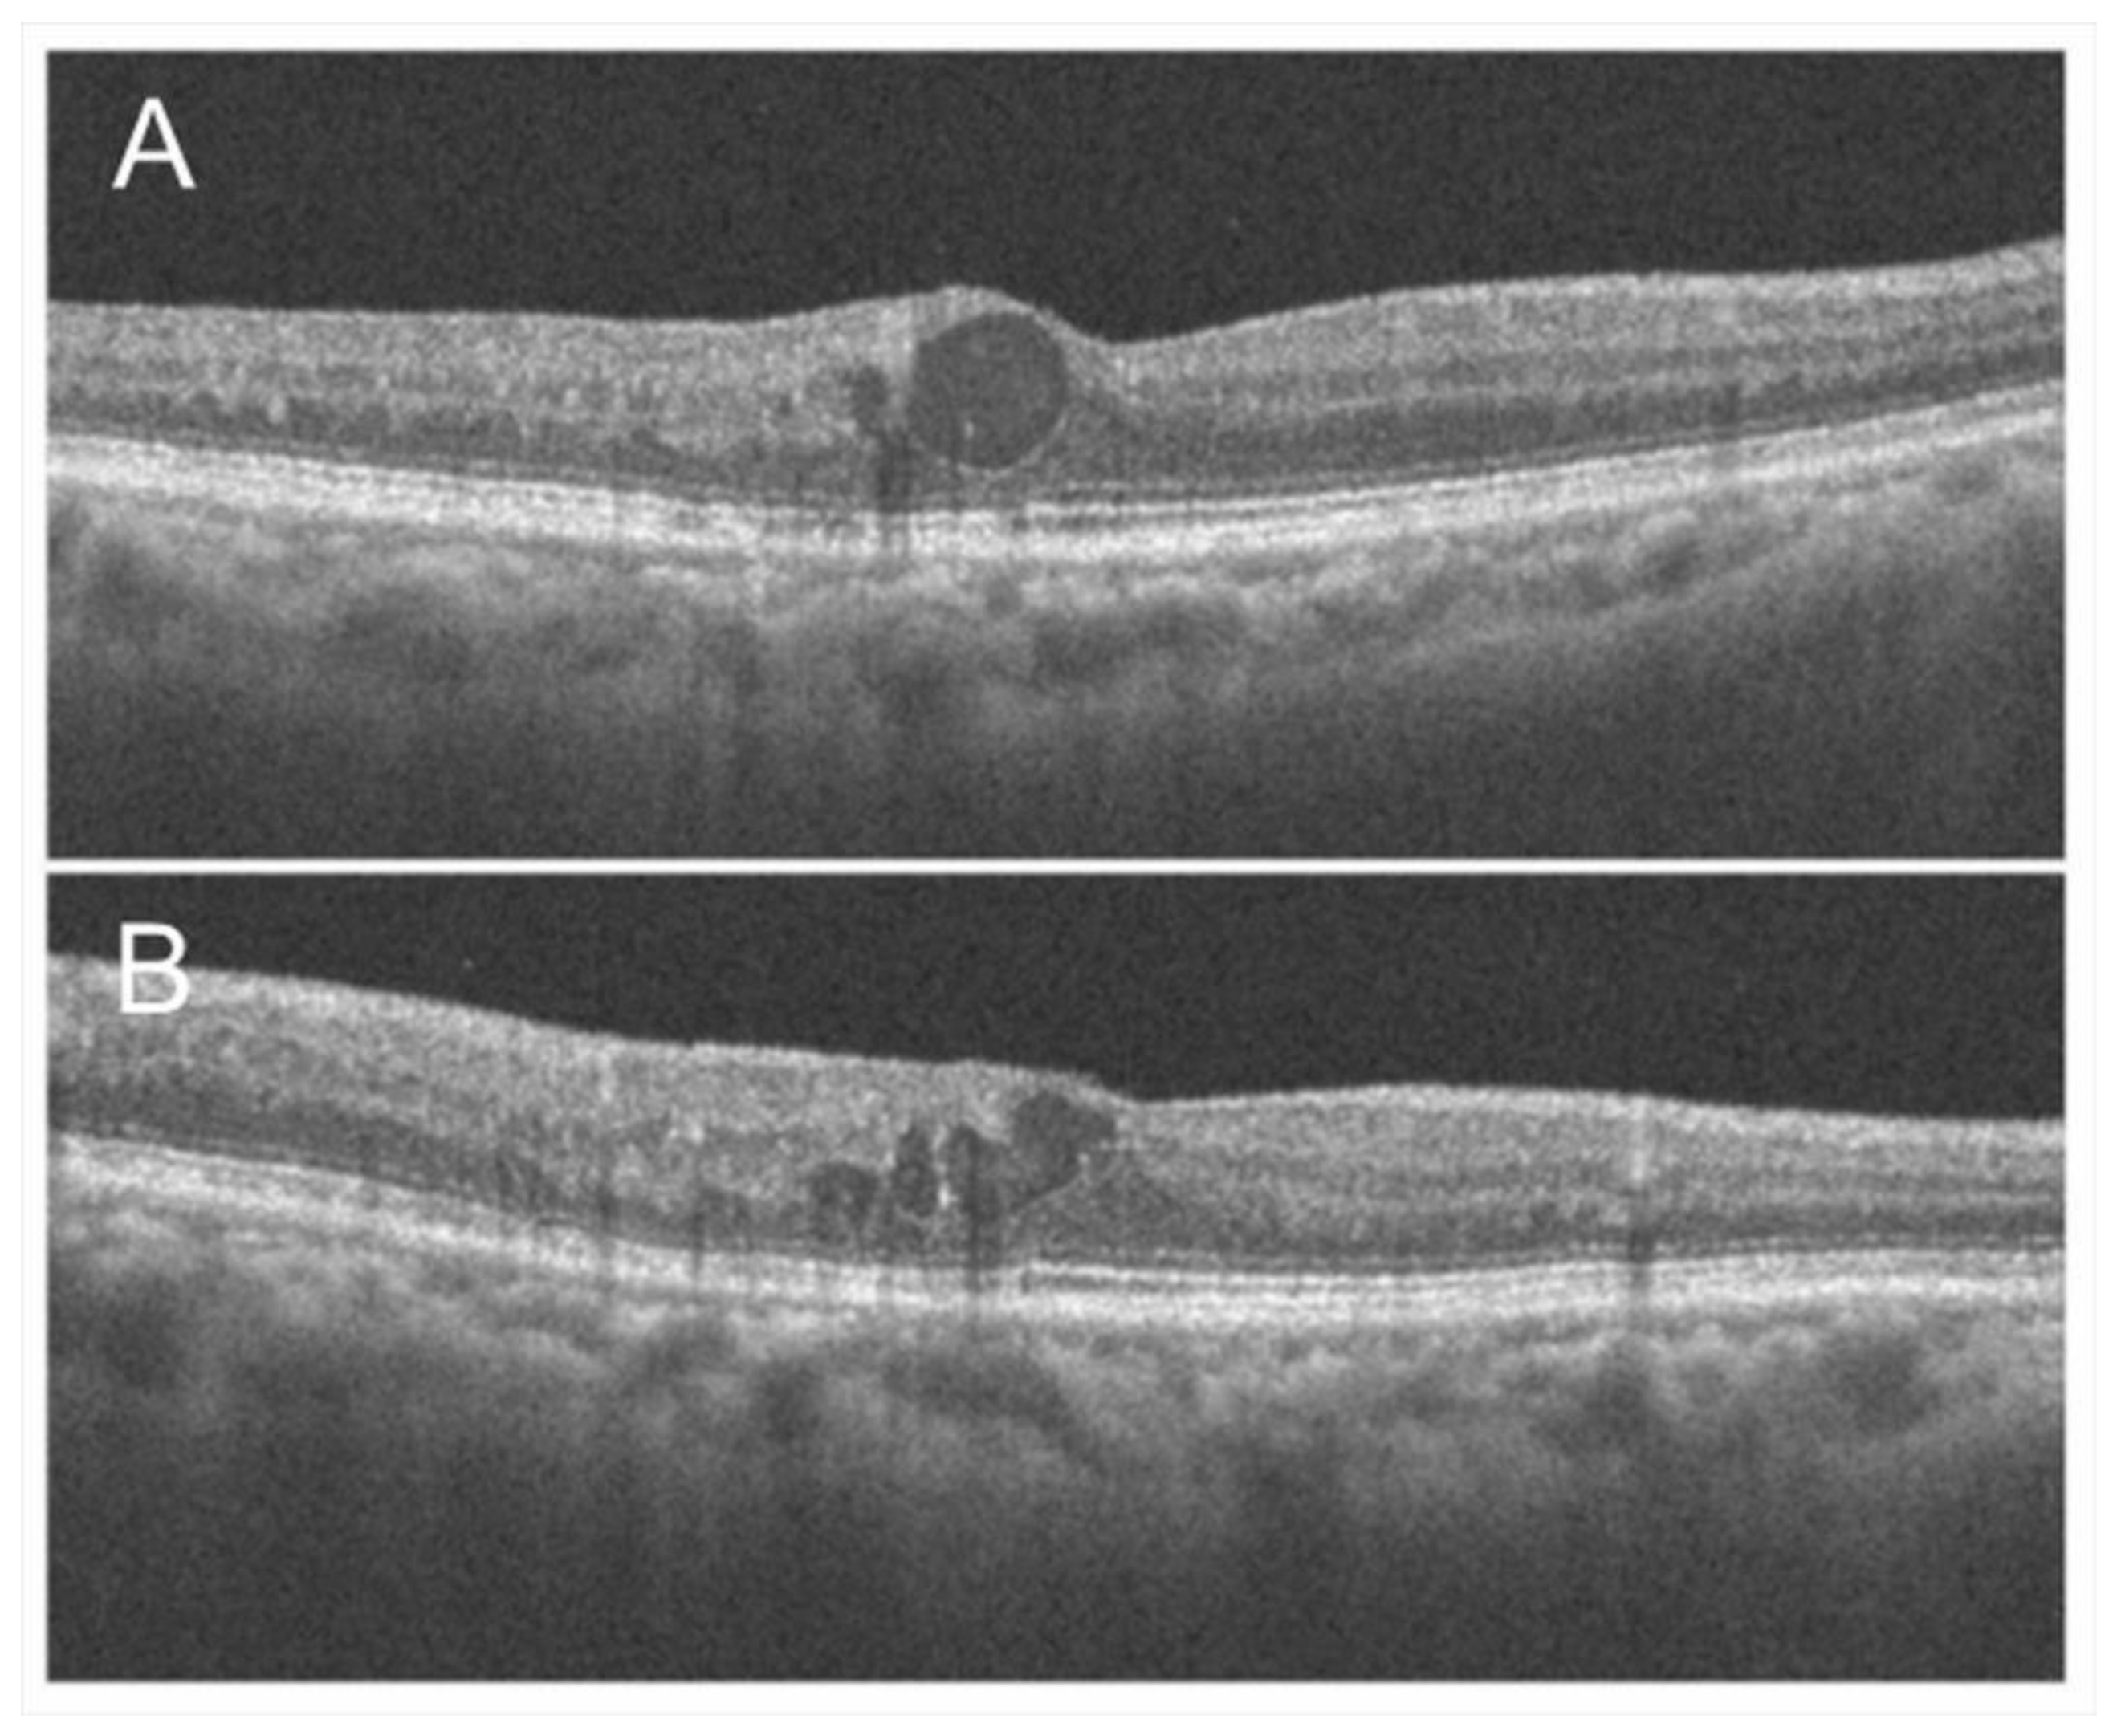

3.8. Microaneurysm and Macroaneurysm

- Hasegawa, T.; Ueda, T.; Okamoto, M.; Ogata, N. Presence of foveal bulge in optical coherence tomographic images in eyes with macular edema associated with branch retinal vein occlusion. Am. J. Ophthalmol. 2014, 157, 390–396.e1. [Google Scholar] [CrossRef]

- Hasegawa, T.; Masuda, N.; Ogata, N. Highly reflective line in optical coherence tomography images of eyes with macular edema associated with branch retinal vein occlusion. Am. J. Ophthalmol. 2015, 159, 925–933.e1. [Google Scholar] [CrossRef]